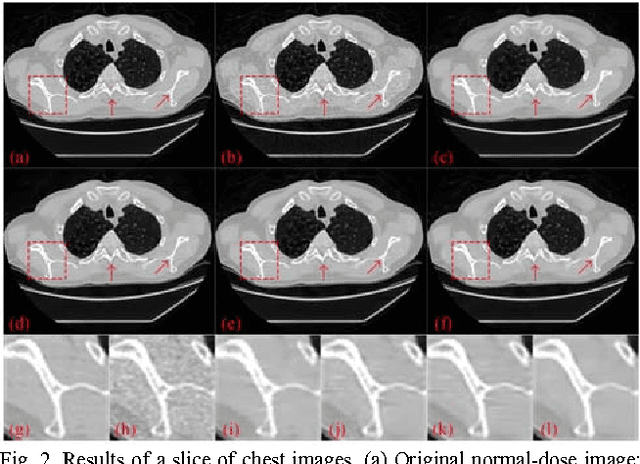

To reduce the potential radiation risk, low-dose CT has attracted much attention. However, simply lowering the radiation dose will lead to significant deterioration of the image quality. In this paper, we propose a noise reduction method for low-dose CT via deep neural network without accessing original projection data. A deep convolutional neural network is trained to transform low-dose CT images towards normal-dose CT images, patch by patch. Visual and quantitative evaluation demonstrates a competing performance of the proposed method.